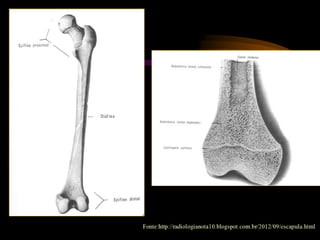

Úmero

Ossos longos

Fonte: SOBOTTA, Johannes. Atlas de Anatomia Humana. 21ed. Rio de Janeiro: Guanabara Koogan, 2000

CARACTERÍSTICA

MACROSCÓPICA DE UM OSSO

LONGO TÍPICO

• Epífises

• Diáfise

• Canal Medular (medula óssea)

• Cartilagem Epifisial (quando em

crescimento)